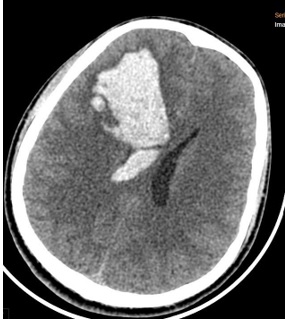

Người bệnh nam, 23 tuổi, trước đó khỏe mạnh. Khoảng 8 giờ sáng ngày 15/4/2026, người bệnh xuất hiện đau đầu đột ngột, sau đó ý thức giảm dần, được phát hiện nằm dưới sàn nhà và đưa đến bệnh viện lúc 13 giờ cùng ngày trong tình trạng lơ mơ, liệt nửa người trái. Kết quả chụp cắt lớp vi tính sọ não cho thấy xuất huyết não bán cầu phải kèm tràn máu não thất. Đây là tình trạng nặng, có nguy cơ đe dọa tính mạng nếu không được xử trí kịp thời.

Hình ảnh xuất huyết não - não thất trên phim chụp CT sọ não